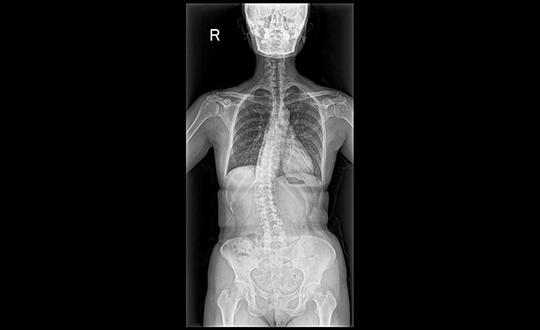

脊椎外科は、整形外科の分野のなかでも、高度な技術と専門性を要求される分野です。主として背骨(脊椎)および背骨の中を通る神経(脊髄)の疾患、外傷、腫瘍を取り扱います。

ISS方式・長尺撮影FPD(富士フイルム)

少ないX線で、鮮明な画像を撮ることができ、長尺撮影により一括撮影が可能。短い時間で検査ができ、体への負担が少ない検査装置。